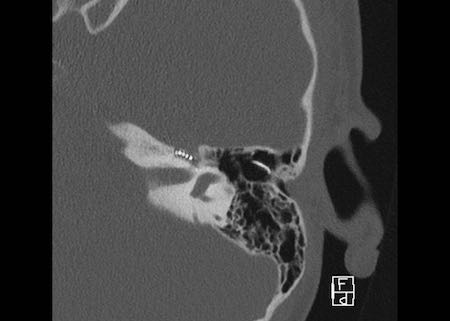

Bên trái là hình ảnh của một bé gái 2 tuổi.

Các hình ảnh từ kết quả chụp CT được thực hiện trước khi cấy ốc tai điện tử.

Quan sát thấy dị dạng nhẹ ở đỉnh ốc tai – không có sự phân tách giữa vòng thứ hai và vòng thứ ba, và trụ ốc tai xương vắng mặt.

Cống tiền đình bình thường.